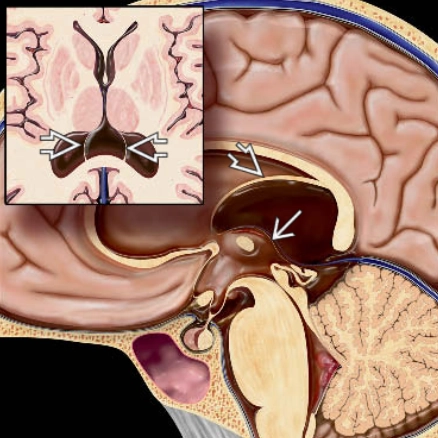

Hẹp cống não (Aqueductal Stenosis)

16/03/2026